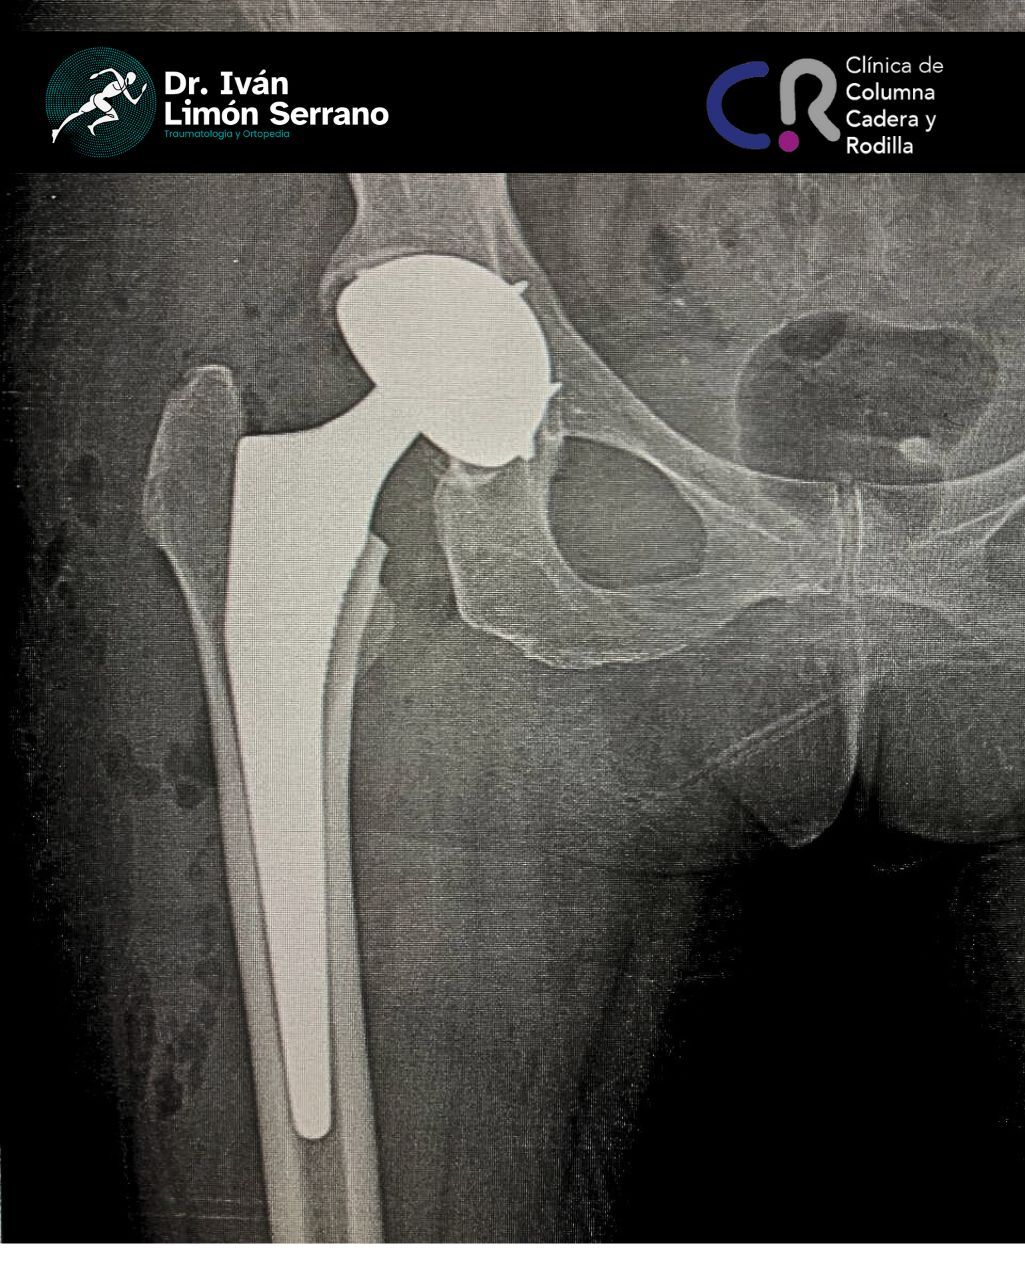

• Prótesis de cadera

• Cirugía cadera

Es una enfermedad articular caracterizada por la por degeneración, perdida del cartílago y alteración del hueso subcondral asociado a cambios en tejidos blandos. Se caracteriza por dolor articular, limitación funcional, crepitación y grados variables de inflamación. Factores de riego como sobrepeso, obesidad, debilidad muscular, actividad física pesada traumatismos, edad avanzada, sexo femenino, factores genéticos, trastornos metabólicos y congénito. Actualmente existen tratamientos desde lo no farmacológico control de peso hasta el tratamiento quirúrgico como lo es el reemplazo articular mediante la colocación de prótesis total.